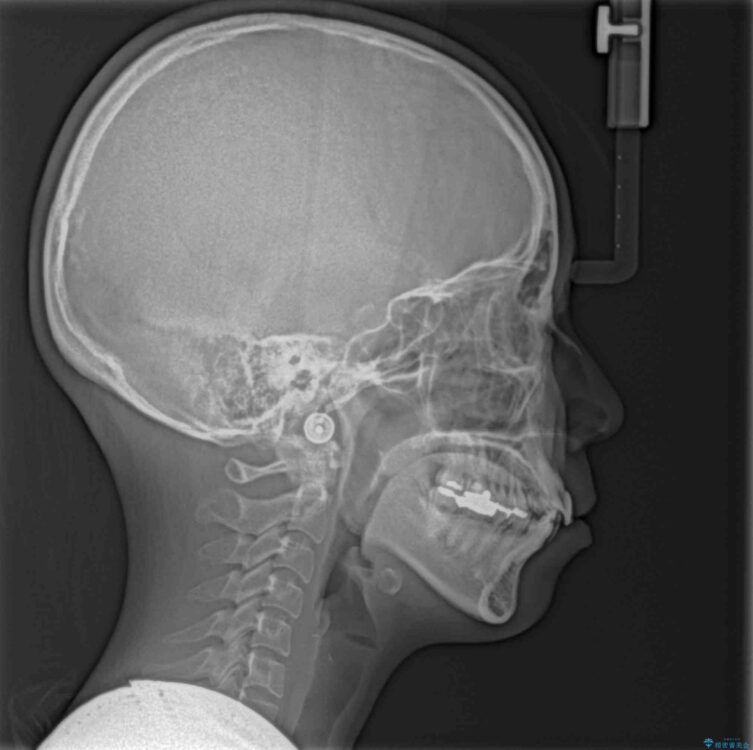

前歯のデコボコと上顎の前突感による口の閉じにくさを気にして来院された患者様です。

治療計画

目立たない装置を希望されたので、上顎が裏側装置のハーフリンガルを選択し、上下左右の小臼歯(計4歯)を抜歯して矯正治療を行うこととしました。